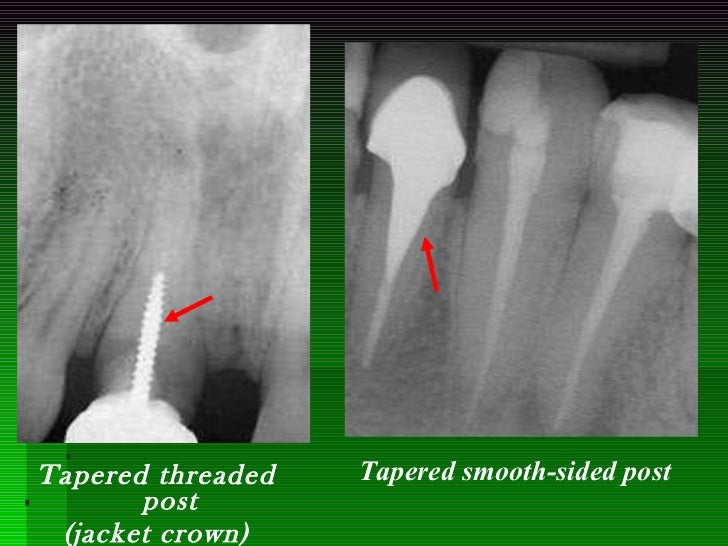

PPT Introduction to Fixed Prosthodontics PowerPoint Presentation What Is The Dowel Crown    crown will allow the use of any dowel and core material. In many instances, inclusion of the. Dental crowns, often just called “crowns” or “teeth caps”, are dental prosthetics that encapsulate a damaged or weakened natural tooth, effectively restoring its shape, size, strength, and appearance.  what is a dental crown?   the dowel length is limited by the. What Is The Dowel Crown.

PPT Introduction to Fixed Prosthodontics PowerPoint Presentation ID What Is The Dowel Crown   what is a dental crown? The availability of various cement shades do minor esthetic corrections. It can improve the way a decayed or broken tooth looks and make it stronger.   the dowel length is limited by the apical seal of four mm to six mm. Dowel width should be as small as possible.  a dental crown is. What Is The Dowel Crown.